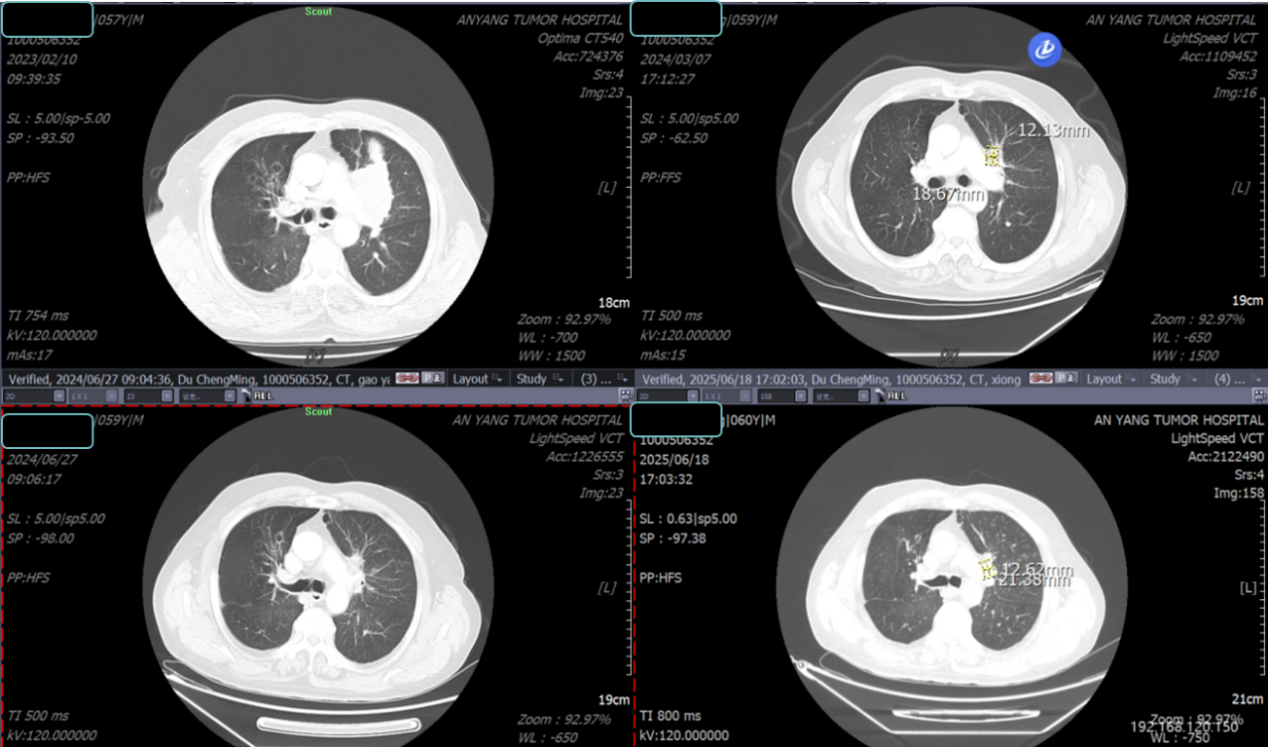

2024年4月至2025年7月,开始口服“长春瑞滨软胶囊 80mg D1/D8/D15,Q21D”。治疗期间复查胸部CT示,病灶较前明显缩小;颈部淋巴结超声示,颈部淋巴结较前缩小(图5);肿瘤指标下降。

14.10.png

图5 颈部超声(2025-06-19)

至2025年7月,患者已坚持治疗15个月,疗效评估:持续PR。

治疗期间疗效评估:

胸部CT:

14.11.png